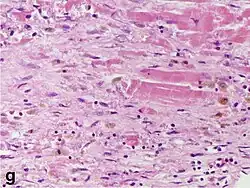

Under the microscope, myocardial infarction presents as a circumscribed area of ischemic, coagulative necrosis (cell death). On gross examination, the infarct is not identifiable within the first 12 hours.[22]

Although earlier changes can be discerned using electron microscopy, one of the earliest changes under a normal microscope are so-called wavy fibers.[23] Subsequently, the myocyte cytoplasm becomes more eosinophilic (pink) and the cells lose their transversal striations, with typical changes and eventually loss of the cell nucleus.[24] The interstitium at the margin of the infarcted area is initially infiltrated with neutrophils, then with lymphocytes and macrophages, who phagocytose ("eat") the myocyte debris. The necrotic area is surrounded and progressively invaded by granulation tissue, which will replace the infarct with a fibrous (collagenous) scar (which are typical steps in wound healing). The interstitial space (the space between cells outside of blood vessels) may be infiltrated with red blood cells.[22]

These features can be recognized in cases where the perfusion was not restored; reperfused infarcts can have other hallmarks, such as contraction band necrosis.[25]

| Macrophages and lymphocytes | 3–5 days | 5–10 days (including 'siderophages') | 10 days to 2 months |    |